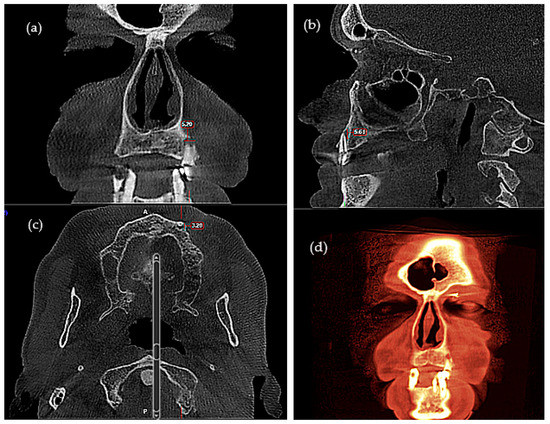

| Horizontal Bone Loss—Max Size | Group | Number | Mean | Standard Average Error | SD | Min | Max | Median | Student’s t Test |

|---|---|---|---|---|---|---|---|---|---|

| OPT | Control | 30 | 4.930 | 0.594 | 3.258 | 0.0 | 13.2 | 4.60 | t = −0.373 |

| ENT Cancer | 33 | 5.191 | 0.367 | 2.109 | 0.0 | 11.3 | 5.00 | p = 0.711 | |

| Total | 63 | 5.067 | 0.340 | 2.698 | 0.0 | 13.2 | 4.80 | ||

| CBCT 3D | Control | 30 | 5.736 | 0.633 | 3.471 | 0.0 | 14.10 | 5.75 | t = −0.548 |

| ENT Cancer | 33 | 6.152 | 0.438 | 2.519 | 0.0 | 12.40 | 6.17 | p = 0.586 | |

| Total | 63 | 5.954 | 0.377 | 2.992 | 0.0 | 14.10 | 6.00 |